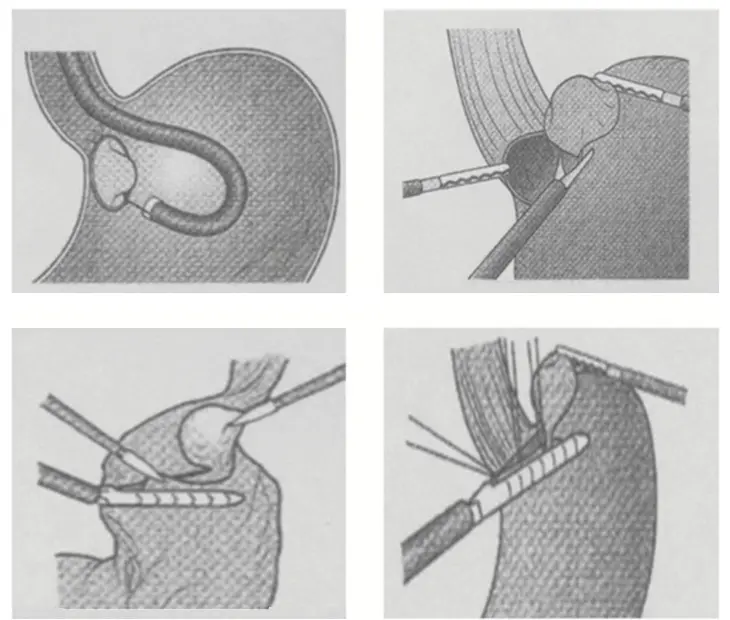

2014年に保険適応となった新しい治療です。粘膜下腫瘍、ESDが困難な早期がんなどを対象とします。

腹腔鏡で消化管の外から、内視鏡で消化管の中からアプローチすることで正確に腫瘍の範囲、位置を確認して切除します。切除範囲を最小限にすることが出来るため、術後の機能障害を抑えることが出来ます。

外科と連携し、この治療に取り組んでいます。術後管理は外科が行っており、入院期間は2週間程度です。

(Hiki, et al. Surg Endosc 2008; 22: 1729-35より引用)